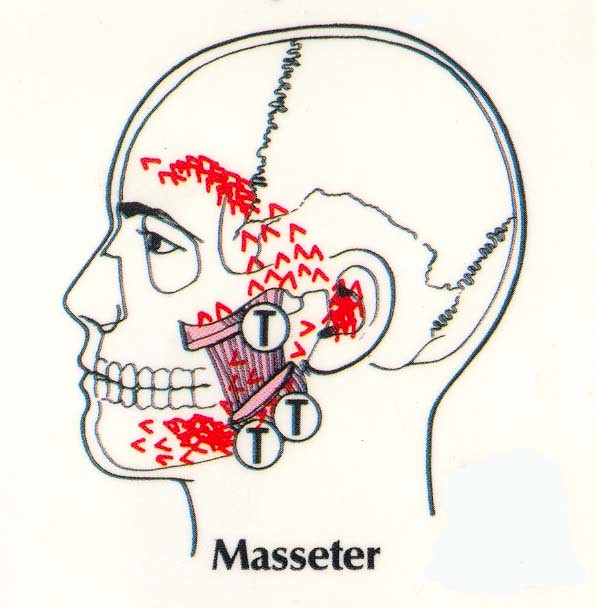

The pano verifies all the maxilla bone issues that include temporal bones at different heights, cloudy left sinus compared to right. Nasal septum is closing off the airway spaces. All the major dentistry is in the upper left. Many patients over the years that have a root canal in the middle of the skeletal asymmetry force like this example have a long history of migraine style headaches especially in the morning.

This patient has multiple issues. Her left neck is chronically tight, the left TMJ is painful, and she has regular left temporal headaches. The teeth were retrofitted between the bones in orthodontics and the continued growth of the mandible onl intensified the wedge. The force on this occlusion has been heavy posterior left all her life. The facial profile matches the shape of the force pattern. The history is mostly pain in the TM joints, pain in the teeth at times, but a lifetime history of left side sinus, temporal and neck pain.